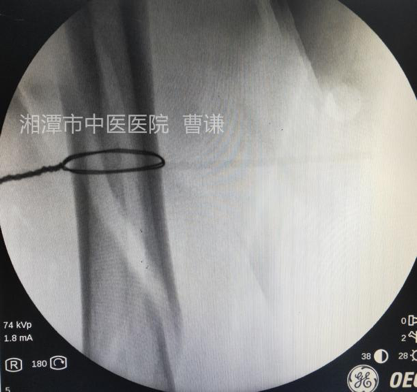

取中号钢丝对折后套入丝线,牵拉丝线另一端将钢丝导入。

有时候分离不充分,牵引线需要较大的力量牵拉,所以牵引线需要粗一点,防止拉断。

在助手维持牵引的同时,使用老虎钳将钢丝拧紧(注意尽量夹持到钢丝结头顶部并提起拧紧)

透视见钢丝逐渐拧紧并使骨折端靠近复位。